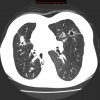

– Giãn phế quản (Bronchiectasis) là giãn không hồi phục một phần của cây phế quản và thường đi kèm với hiện tượng dày thành phế quản và ứ đọng chất nhầy. Có thể giãn ở phế quản lớn trong khi phế quản nhỏ vẫn bình thường hoặc giãn ở phế quản nhỏ trong khi phế quản lớn bình thường.

– Bình thường khẩu kính phế quản ngang với khẩu kính động mạch đi kèm. Trường hợp giãn phế quản, khẩu kính của phế quản sẽ lớn hơn động mạch đi kèm.

– Giãn dạng khu trú hay gặp nhất. Thường gặp ở các phân thùy đáy sau (50%), thùy giữa hoặc thùy lưỡi (10%)